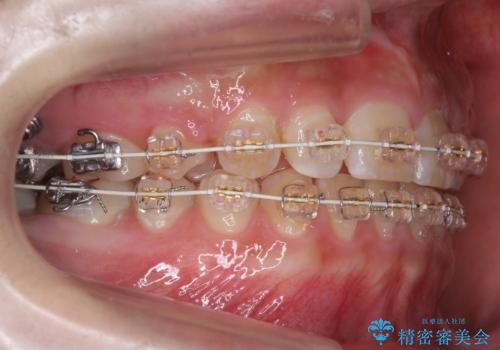

- 矯正装置

- 審美装置

- 上の小臼歯を2本抜歯して矯正を行いました。

奥歯のかみ合わせが、歯と歯が向かい合わせになっておりまた、歯ぎしりも多い方で装置の脱離も頻繁にありました。

ワイヤー矯正ではやや難しい症例でした。

ご自身でしっかり装着しなければならないですが、非抜歯で上顎を遠心移動するのであれば、マウスピース矯正も有用な症例だと思います。ただし、右側の2級関係が厳しいため、遠心移動量がかなり大きくなりそうです。どう治すにしても時間がかかりそうな症状です。